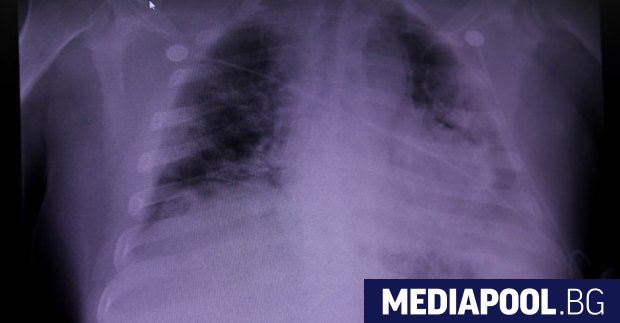

... и прескачане на сърцето, пише DW."При белодробните отклонения пък наблюдаваме най-вече увреждания на белодробната тъкан, в резултат на което възниква злокачествена обмяна на газове", посочи Букерт.

Белите дробове са основната мишена на новия коронавирус COVID 19 Най често

Видео разкрива увреждане на белите дробове при пациент с коронавирус

...... да премахнат въглеродния диоксид. Това би причинило пациентът да се задъхва или да вдишва много въздух, за да балансира нивата на кислород и въглероден диоксид.